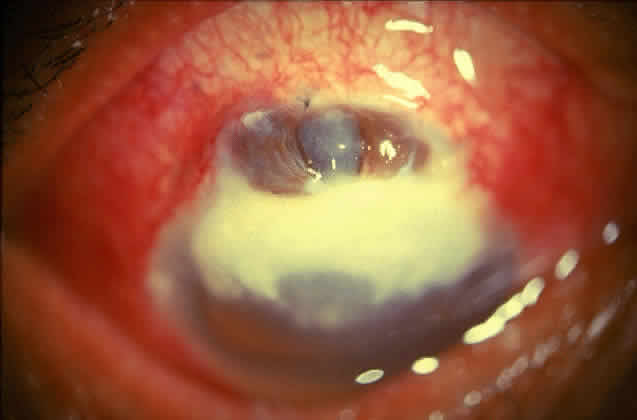

Active corneal infections in advanced stages are encountered more often by corneal surgeons in developing countries compared with their counterparts in developed countries (Fig. 8). The extent of corneal involvement associated with other intraocular damage often compromises the success of corneal transplantation. In a series from our institution, the success rate for graft clarity was poorer24 compared with other series.25 Ophthalmologists involved in corneal surgery should be familiar with this information and be prepared for the necessary intraoperative manipulations (Fig. 9).

Fig. 8. Corneal ulcer with extensive necrosis and perforation in the superior part.

Fig. 9. Large central perforation in a case of infectious keratitis.